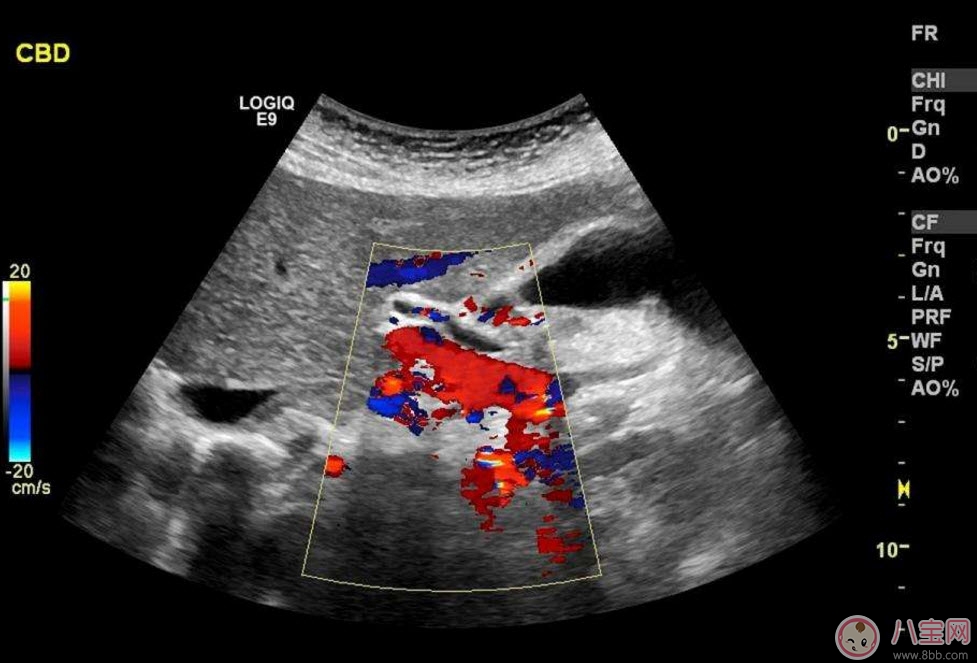

??B超也稱為二維超聲,分為黑白的和彩色的兩種。 彩超其實(shí)還是黑白的,彩超簡(jiǎn)單的說就是高清晰度的黑白B超再加上彩色多普勒,既具有二維超聲結(jié)構(gòu)圖像的優(yōu)點(diǎn),又提供了血流動(dòng)力學(xué)的豐富信息。彩超的分辨率會(huì)比一般黑白B超高一些,所以在需要做比較細(xì)致的檢查的時(shí)候,更多的醫(yī)生愿意通過彩超來檢查。例如,因?yàn)椴食苡貌噬珮?biāo)注血流,所以當(dāng)臍帶繞頸的時(shí)候就會(huì)看見寶寶的脖子上呈U形或者W形的血流,對(duì)是否臍帶繞頸也就一目了然了。目前用于產(chǎn)檢的超聲波一般都是二維的。

除了能觀察到通過B超觀察到的一切外,彩超能夠直觀成像,顯示更清晰,結(jié)果也更快速,可發(fā)現(xiàn)異常血流,為診斷胎兒先天性心臟缺陷提供了診斷依據(jù)。價(jià)格要比B超貴,大概在150元左右(會(huì)根據(jù)各地具體情況的不同而上下浮動(dòng))。二維彩超適用于整個(gè)孕期,特別是臨產(chǎn)前。二維彩超的圖像也并非就是彩色的,而是用彩色標(biāo)注心臟、血流等指標(biāo),其實(shí)就是高清晰度的黑白B超再加上彩色多普勒。觀測(cè)到的圖像以紅藍(lán)兩色血流方向?yàn)橹鳎嫦蛱筋^的呈現(xiàn)紅色,反之為藍(lán)色。這種技術(shù)能夠觀測(cè)到胎兒的血液流動(dòng)情況,有利于及時(shí)發(fā)現(xiàn)胎兒的異常。比如,發(fā)現(xiàn)胎兒頸部有血流環(huán),則意味著發(fā)生了可導(dǎo)致窒息死亡的臍帶繞頸。